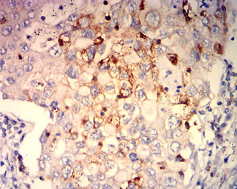

ITGB7 Mouse Monoclonal antibody[1B4A8]

Immunogen:    Purified recombinant fragment of human ITGB7 (AA: 20-174) expressed in E. Coli.

IHC    1/200 - 1/1000